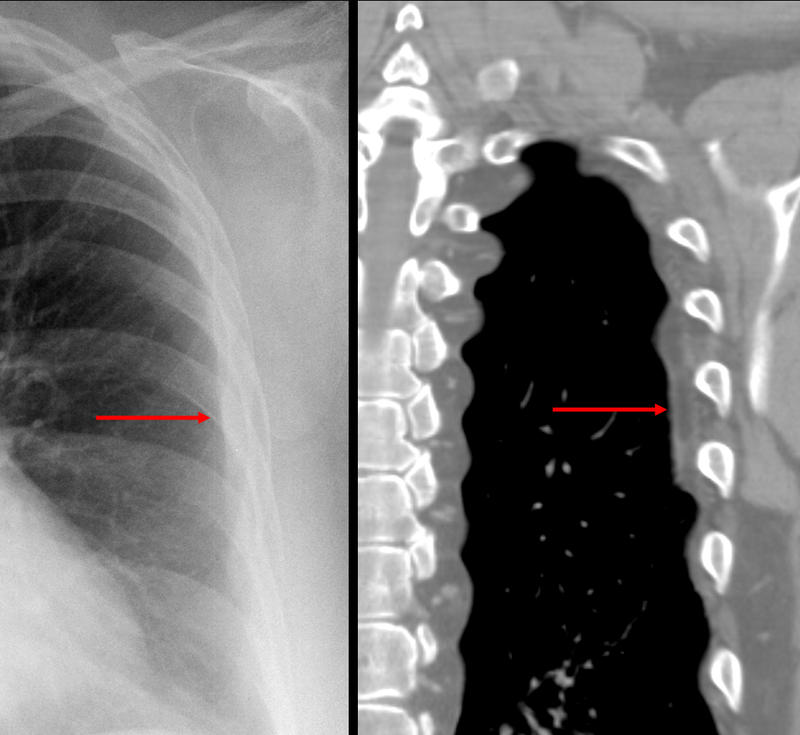

Gallery Pleural subpleural fat

subpleural fat